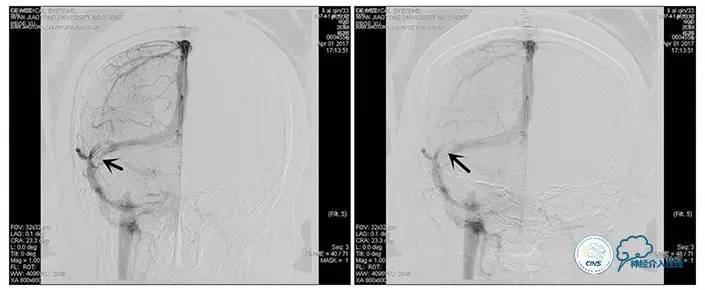

右侧ICA正位

右侧ICA侧位

术中造影

5ml/s,总量8ml,压力100~150

术后造影

术毕远近端压力差为:0